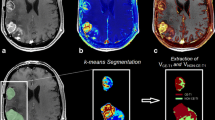

“differential maps” from serial T1 mapping (Fig. 1, upper row) and

Fig. 1 Diff maps and subtraction maps. In the Diff maps (upper row), voxelwise subtraction of the T1 relaxation time (according to the formula (T1 without CA of time-point x − T1 without CA of time-point 1) / T1 without CA of time-point 1) is performed from two different time points. Time-point 1 indicates the first time point after starting bevacizumab therapy, this time point indicates the baseline for further monitoring. In the subtraction maps (lower row), voxelwise subtraction of the T1 relaxation time is performed from one time point but with and without contrast agent (according to the formula (T1 without CA − T1 with CA) / T1 without CA). The relative shortening of T1 after application of contrast agent quantifies the “contrast enhancement”

“subtraction maps” from one time point, subtracting contrast-enhanced T1 maps from non-contrast T1 maps (Fig. 1, lower row).

The changes of relaxation times on differential maps were color-coded, with yellow/red for an increase in relaxation times and green/blue for the shortening (Fig. 1, upper row).

The maps should indicate the shortening of T1 relaxation time upon the accumulation of contrast agent within the tumor tissue. The T1 relaxation time maps which were acquired before application of contrast agent were coregistered with the contrast-enhanced T1 relaxation time maps of the same MR examination and then a voxelwise subtraction according to the formula ((T1-pre-CA − T1-post-CA) / T1-post-CA) was performed (Fig. 1, lower row).